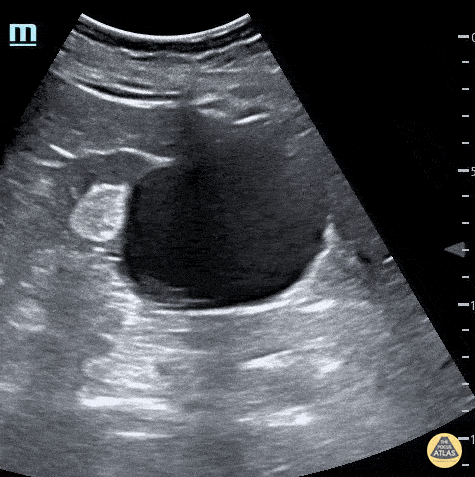

Large Renal Cyst seen coming off of the kidney in short axis. Dax Spencer